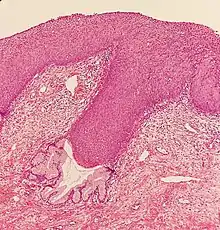

Classification

Historically, abnormal changes of cervical epithelial cells were described as mild, moderate, or severe epithelial dysplasia. In 1988 the National Cancer Institute developed "The Bethesda System for Reporting Cervical/Vaginal Cytologic Diagnoses".[12] This system provides a uniform way to describe abnormal epithelial cells and determine specimen quality, thus providing clear guidance for clinical management. These abnormalities were classified as squamous or glandular and then further classified by the stage of dysplasia: atypical cells, mild, moderate, severe, and carcinoma.[13]

Depending on several factors and the location of the lesion, CIN can start in any of the three stages and can either progress or regress.[1] The grade of squamous intraepithelial lesion can vary.

CIN is classified in grades:[14]

| Histology Grade | Corresponding Cytology | Description | Image |

|---|---|---|---|

| CIN 1 (Grade I) | Low-grade squamous intraepithelial lesion (LSIL) |

|

| CIN 2/3 | High-grade squamous intraepithelial lesion (HSIL) |

| CIN 2 (Grade II) |

| CIN 3 (Grade III) |